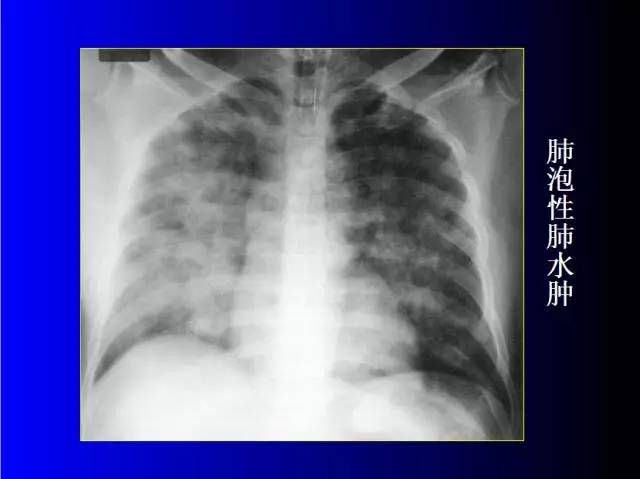

肺部基础X片及CT片解读